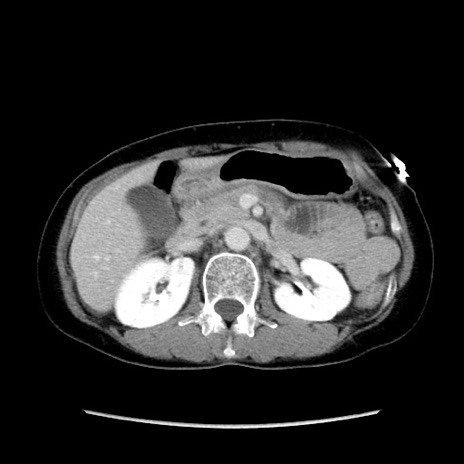

症例32(横断像)

【症例】40歳代 女性

【主訴】上腹部痛、嘔気・嘔吐

【現病歴】約9時間前頃から急に上腹部痛、嘔気、嘔吐が出現。改善しないため救急要請。

【既往歴】子宮頚癌(広汎子宮全摘術、放射線療法)、腸閉塞

【身体所見】腹部:平坦、軟、腸雑音亢進、上腹部を中心に腹部全体に圧痛あり。

【データ】WBC 8400、CRP 0.03